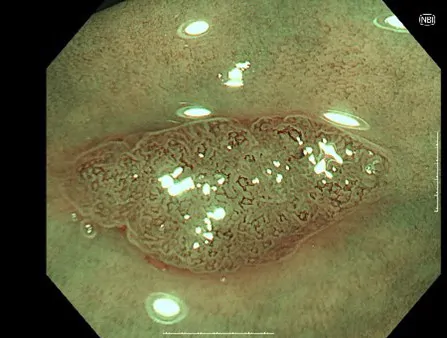

NBI(狭帯域光観察)

がんの増殖には血管からの栄養補給を必要とするため、病変の近くの粘膜には、小さな血管が集まりやすくなります。そのため、この小さな血管の集まりをいち早く発見することが、がんなどの病変の早期発見には重要です。

そのために用いられる技術が、「NBI(Narrow Band Imaging)」です。NBIは、血液中のヘモグロビンに吸収されやすい紫と緑の2つの特殊な光を照らすことで、粘膜表層の毛細血管やそのパターンなどが強調して鮮明に表示される観察技術です。これにより、通常光による観察では見えづらかったがんなどの病変の早期発見に貢献することが期待されます。

また、最適な治療判断には病変診断も重要となります。NBIは血管や粘膜の詳しい観察をサポートし、その診断にも貢献することが期待されます。

大腸カメラの症例